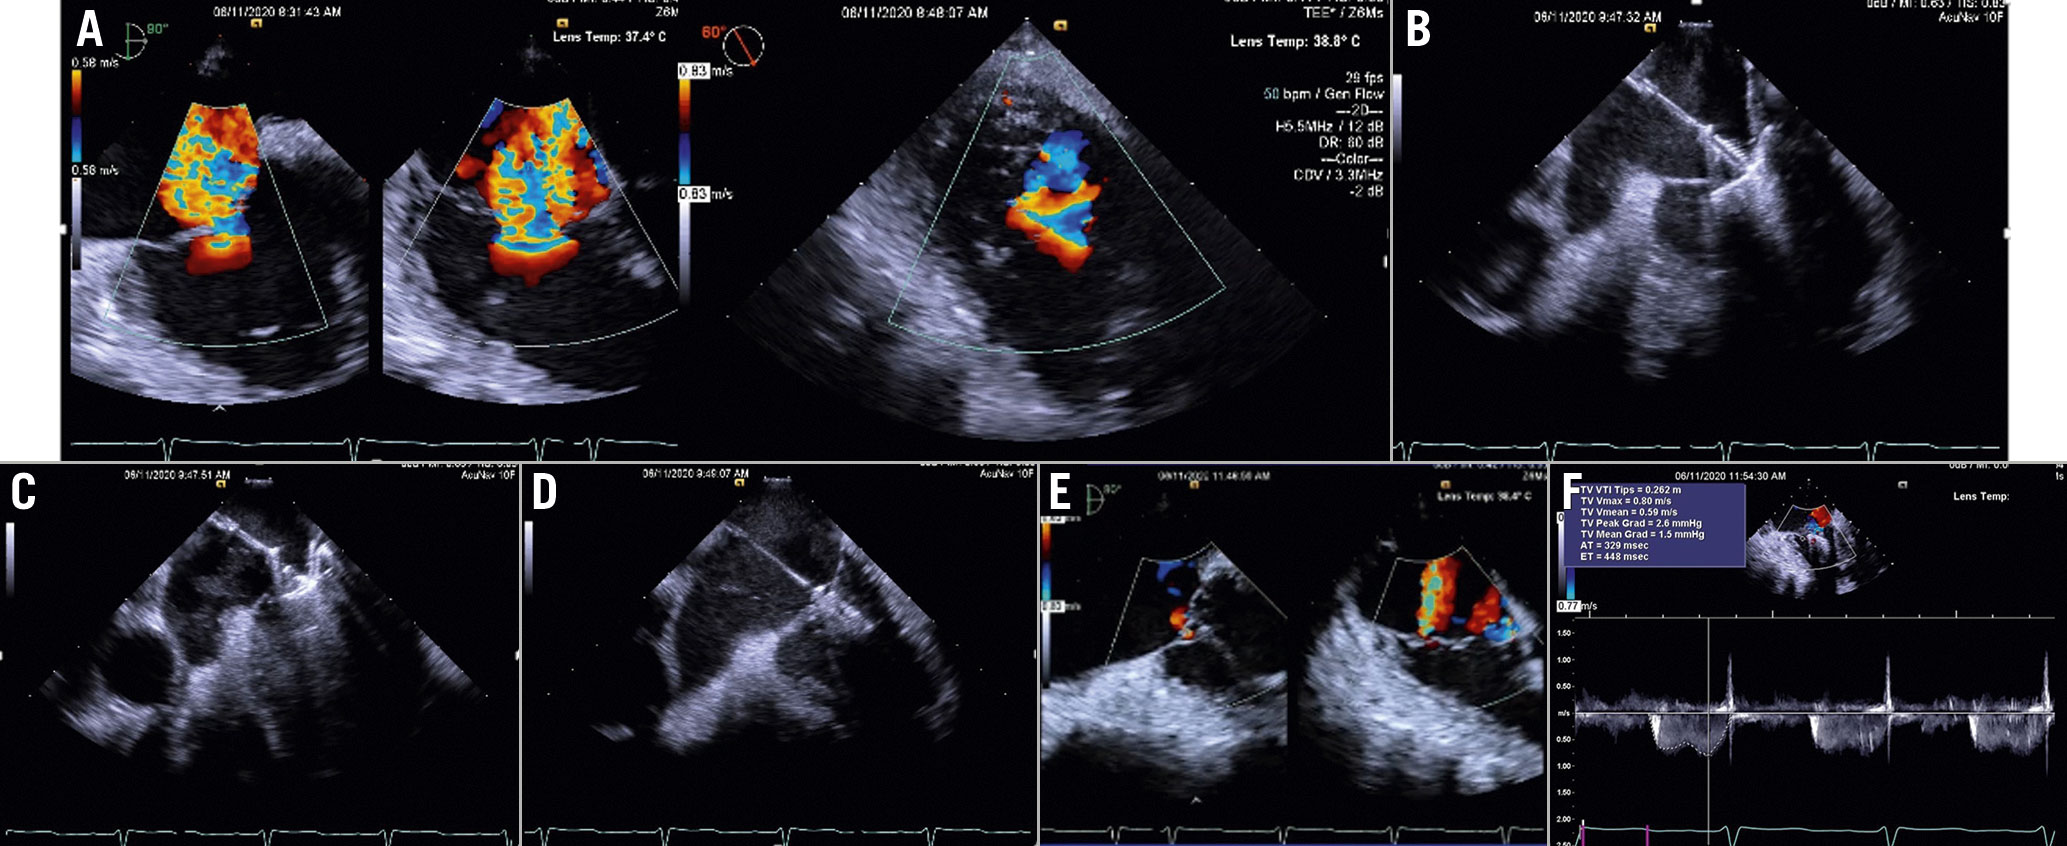

Leafletapproach

The rationale behind TV leaflet approximation (TriClip[Abbott Laboratories] and PASCAL systems) is to restore coaptation between leaflets and reduce the regurgitant orifice area. The procedural steps and imaging guidance are shown in Figure 14-Figure16 and Supplementary Table 9.

Figure 14. TriClip procedure. A) Baseline evaluation. B) GC insertion into the RA. C) Steering manoeuvre towards the TV plane and trajectory (LAX transgastric view). D) CDS advancement into the RV (biplane transgastric views). E) Clip arm orientation (SAX transgastric view). F) Leaflet grasping. G) Residual TR after first clip implantation (SAX transgastric view). H) Assessment of leaflets insertion. I) Second clip implantation. J) Result after second clip. K) Transvalvular gradient.CDS: clip delivery system; GC: guide catheter; RA: right atrium; RV: right ventricle; SAX: short axis; TR: tricuspid regurgitation

Figure 15. TriClip procedure guided by ICE. A) Baseline evaluation. B) Clip advancement into the RV. C) Leaflet grasping. D) Assessment of leafletinsertion. E) Final result. F) Transvalvular gradient. Courtesy of Mani Vannan, Marcus Heart Valve Center, Piedmont Heart Institute, Atlanta, USA. MV: mitral valve